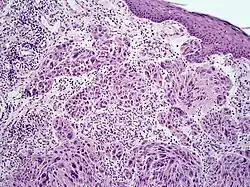

Melanoma with features of a Spitz nevus

| Spitzoid melanoma | |

Melanoma with features of a Spitz nevus, also known as a Spitzoid melanoma, is a cutaneous condition characterized histologically with tissue similar to a spitz nevus and with overall symmetry and a dermal nodule of epithelioid melanocytes that do not mature with progressively deeper dermal extension.[1]